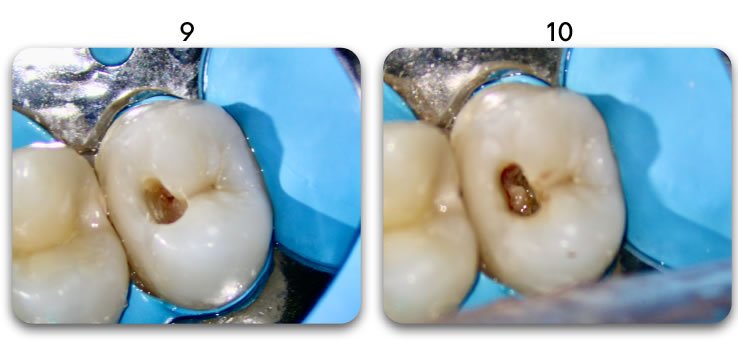

Excellent light transmission

Excellent light transmission for use with dual-cure resins, Biolight DUAL offer excellent light transmission through the optic fiber material.